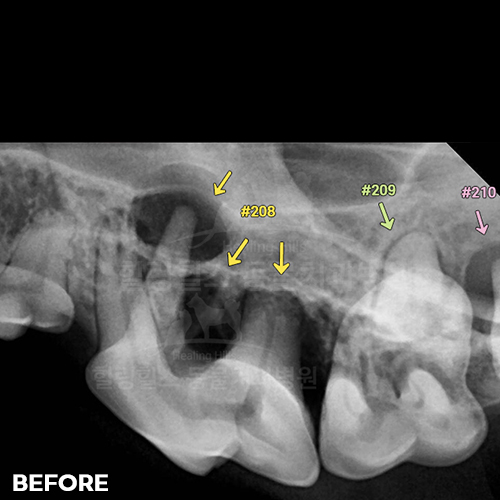

[1.7kg 초소형견 턱뼈에 금이 가게 하고 구멍을 내는 강아지치주염 - 안전발치]

샘플